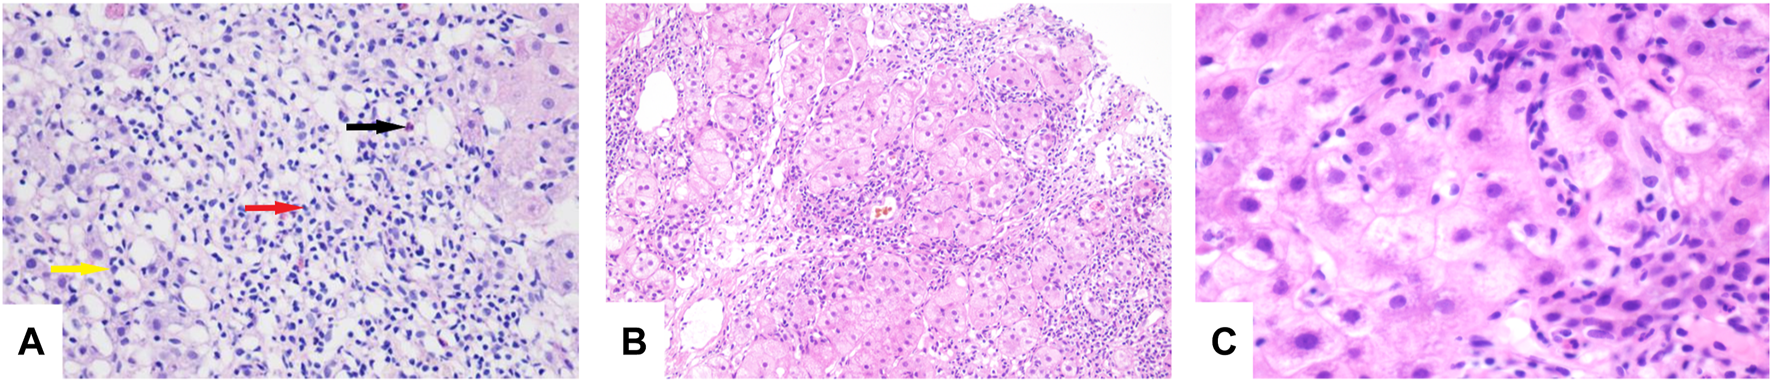

FIGURE 1. (A) Lymphocytes (red arrow), eosinophils (black arrow), and neutrophils (yellow arrow) seen in the portal duct area (HE, original magnification × 200). (B) “Rose garland” formation (HE, original magnification × 100). (C) Lymphocytes “penetrate” (HE, original magnification × 600).

His chest CT showed resolution of the lung lesions after 85 days of treatment, and voriconazole was discontinued on 10 November 2020. On 31 May 2021, laboratory studies revealed TBil, 11.9 μmol/L; ALT, 52 U/L; AST, 40 U/L; ALP, 204 U/L; and γ-GT, 93 U/L. A repeat liver biopsy after 24 weeks of treatment was consistent with autoimmune-like phenomenon liver failure (G3 S3) (Figures 1B,C). A diagnosis was made according to the Roussel Uclaf Causality Assessment Method (RUCAM) (Danan and Benichou, 1993), and a probable diagnosis of autoimmune hepatitis was made based on 2008 International Autoimmune Hepatitis Group’s (IAIHG) criteria (Hennes et al., 2008): (1) DILI, cholestatic, acute, and RUCAM score calculated as 10 (highly likely); (2) IAIHG score 4, combined with liver pathology, the diagnosis of the teenager is drug-induced liver injury with autoimmune-like phenomenon (AL-DILI), drug-induced autoimmune hepatitis (DI-AIH) is not excluded.

The patient developed hepatic encephalopathy and frequent vomiting on day 4, and she was placed on the liver transplant waiting list. She was treated with dexamethasone (10 mg q.d. i.v., gradually decreased after 3 days), liver protection, and NBAL (from July 7 to July 20, once every 3–4 days), and her liver function rapidly improved. After 10 days in a comatose state, she regained consciousness. She continued to have an intermittent low-grade fever on 24 July 2020, and no cough or other symptoms. Her TBil level had increased to 388 μmol/L, and the white blood cell (WBC) count was 12.13 × 109/L with 83.50% neutrophils. Her chest CT scan showed multiple nodules in both lungs on July 26 (Figures 3A,B), and IFI was diagnosed. A loading dose of caspofungin of 70 mg q.d. ivgtt was given on the first day, and then it was continued at a dose of 35 mg/d ivgtt for 23 days. However, a repeat chest CT showed an increase in the number of lung lesions and the presence of an air crescent sign (Figures 3C,D). Bronchoalveolar lavage fluid (BALF), G test, GM test, and next-generation sequencing (NGS) were all negative; however, based on her history and chest CT findings, a diagnosis of IPA was highly likely. Caspofungin was changed to voriconazole (loading dose on D1 of 6 mg/kg daily q12 h ivgtt, maintenance dose of 4 mg/kg q12 h orally was started on D2) on 19 August 2020, and her liver function gradually improved. A liver biopsy on 25 August 2020 was consistent with DILI (G 3–4 S 3–4) (Figures 4A,B). She was discharged on oral voriconazole (250 mg, q12 h), methylprednisolone (4 mg, q.d.), and other medications. A second liver biopsy after 10 weeks revealed an autoimmune-like phenomena hepatitis (G 1–2 S 2–3) (Figures 4C,D). A liver biopsy was performed, and ink staining, periodic acid–Schiff staining, hexamine silver staining, acid-fast staining, and NGS of liver tissue were negative. A diagnosis of DILI was made according to the RUCAM and 2008 IAIHG criteria: (1) DILI, hepatocellular damage-type, acute, RUCAM score calculated as 9 (highly likely); (2) IAIHG score 4, the diagnosis of DILI with autoimmune-like phenomena.

FIGURE 4. (A) Bridging or submass necrosis of hepatocytes and residue liver cells were arranged in a pseudolobule-like pattern, some of which had macrovesicular steatosis (<10%), and moderate to severe interfacial inflammation were noted (HE, original magnification × 40). (B) The portal duct area was obviously enlarged, interlobular bile duct hyperplasia was present, and portions of the bile ducts were slightly dilated with bile thrombosis. Infiltration of numerous mixed inflammatory cells into the interstitium, and fibrous tissue hyperplasia accompanied with partial pseudolobule formation was also noted (HE, original magnification × 100). (C) “Rose garland” formation (HE, original magnification × 40). (D) Lymphocytes “penetrate” (HE, original magnification × 200). (E,F) Slight edema and degeneration in hepatocytes, scattered with spotty necrosis. Infiltration of a small number of mixed inflammatory cells into the interstitium and fibrous tissue (HE, original magnification × 40).

In order to confirm the diagnosis and efficacy, we performed a third liver biopsy a year later (12 August 2021). The liver histopathology indicated chronic hepatitis (G 1 S 2) (Figures 4E,F), which was significantly improved compared with the previous two. No autoimmune-like phenomena were observed. Therefore, we have discontinued glucocorticoids on 18 August 2021. After 406 days of voriconazole treatment, the pulmonary nodules were completely absorbed.